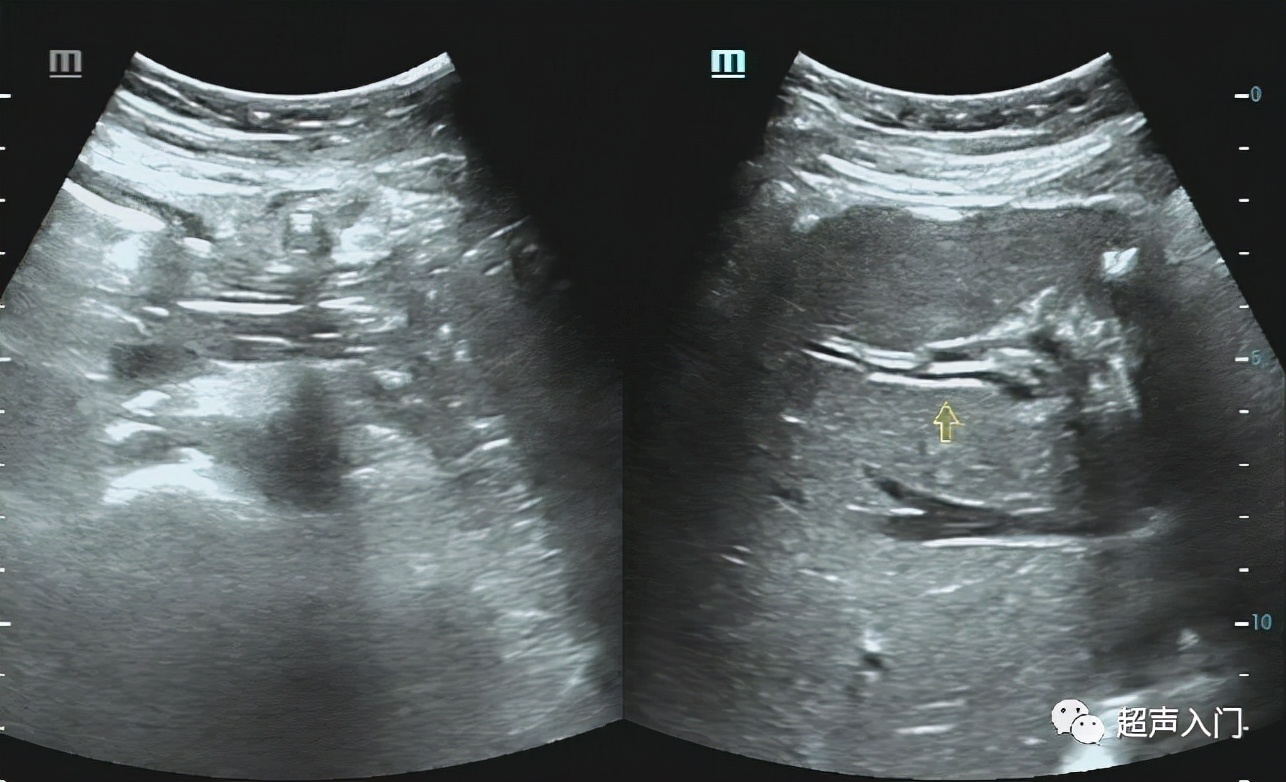

05 肝内胆管扩张

(著名的“平行管”征)